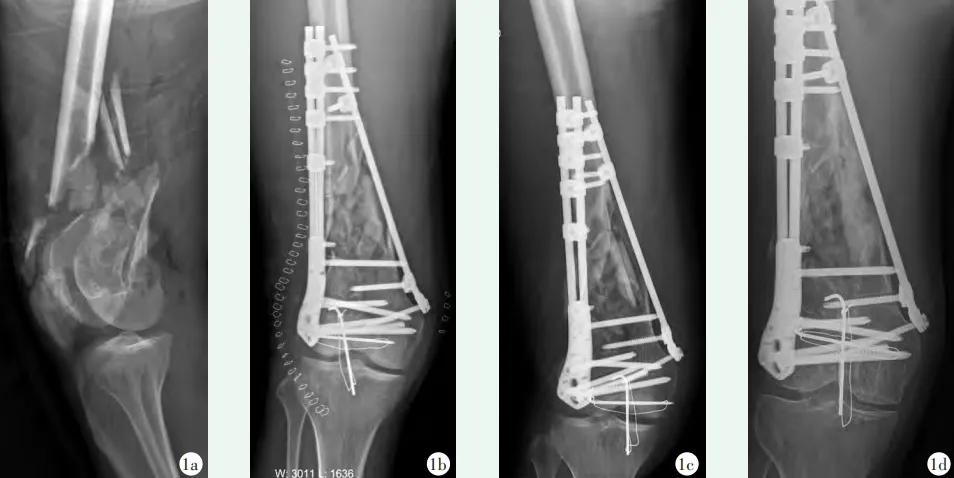

图6 患者,男,40岁,右股骨远端骨折,AO分型C2型,行BCFS混棒固定手术治疗,同时合并髌骨骨折,行克氏针张力带手术治疗。1a:术前X线片示右股骨远端骨折合并髌骨骨折;1b:术后X线片提示骨折线位良好,内固定稳定;1c:术后1个月X线片提示内固定未见松动,骨折复位未见丢失;1d:末次随访X线片提示骨皮质连续,骨折愈合。